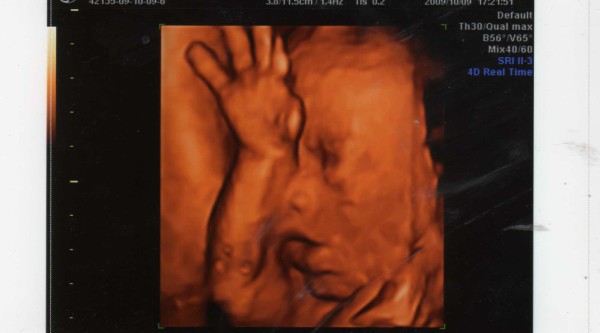

Ultrahangon minden rendben volt, Tesóka nagyon jól van! Holnap feltöltöm a képet a gépre, és akkor megmutatom, bár mélyen a placentába volt az arca a Drágámnak